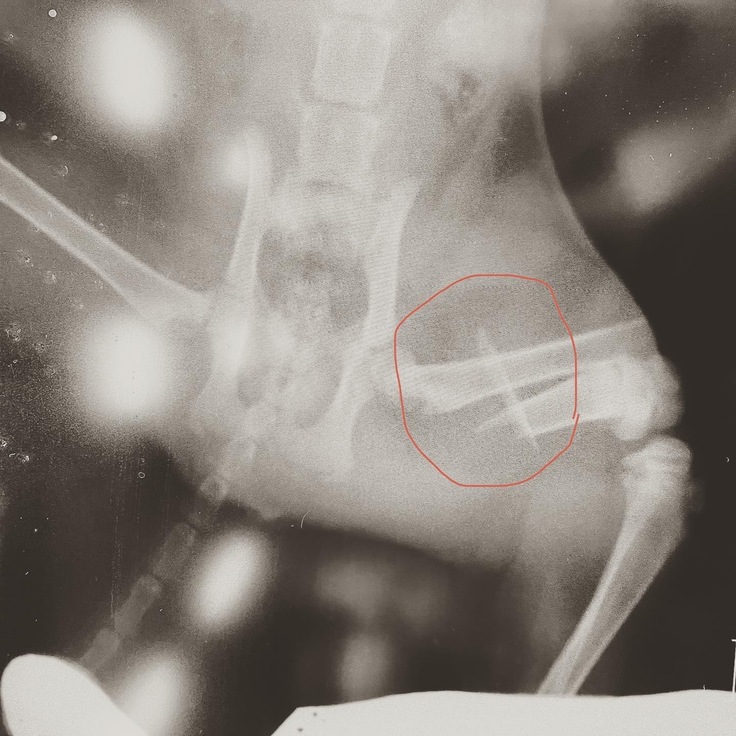

縫合後の皮膚の治りは順調です。骨も少しずつですが、くっついてきています。しかし固定したピンがズレてきているため、皮膚を突き抜け、飛び出してくる可能性があるとのことでした。飛び出してきた場合はまた抜き取る処置をしなくてはならないとのことでした。次の受診は9/11を予定しています。

④定期受診(9月11日)

レントゲン撮影を行いました。

骨は綺麗に治ってきています‼︎

しかしピンの位置がズレてきていて、このままでは皮膚を突き破るので、そうなる前にピンを取り除くため、再手術を行うことになりました。本来であればピンを温存する予定でしたが、今の骨の状態であればピンを取り除いても大丈夫とのことでした。

次の受診日の9月16日に再手術を行う予定です。

8月20日に手術をした時には膝関節から大腿骨にかけてピンを入れてましたが、今はピンの位置がズレいて、お尻の皮膚が盛り上がり、突き破りそうになっています。

8月31日と9月11日に撮ったレントゲンを比べても、かなりピンの位置が違います。

↓[8月31日撮影]

↓[9月11日撮影]